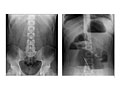

Abdominal X-Ray

Test OverviewAn abdominal

X-ray is a picture of structures and

organs in the belly (abdomen). This includes the

stomach, liver, spleen, large and small intestines, and the diaphragm, which is

the muscle that separates the chest and belly areas. Often two X-rays will be